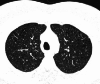

Objectives: Pulmonary Langerhans cell histiocytosis (PLCH) is a rare interstitial granulomatous disease that usually affects young adults who are smokers. Chest computed tomography (CT) allows a confident diagnosis of PLCH only in typical presentation, when nodules, cavitated nodules and cysts coexist and predominate in the upper and middle lungs.

Results: PLCH can present with some aspecific features that may cause diagnosis of the initial disease to be overlooked or other pulmonary diseases to be suspected. In cases of nodule presentation alone, the main differential diagnosis should include lung metastasis, tuberculosis and other infections, sarcoidosis, silicosis and Wegener's disease. In cases of cysts alone, the most common diseases to be differentiated are centrilobular emphysema and lymphangiomyomatosis. Clinical symptoms are usually non-specific, although a history of cigarette smoking, coupled with the presence of typical or suggestive findings at imaging, is key to suspecting the disease. Atypical presentations require surgical biopsy for diagnosis.

Teaching points: • PLCH is a rare interstitial smoking-related disease that usually affects young adults. • The typical first CT shows a mix of nodules, cavitary nodules and cysts in the upper-middle lungs. • Atypical appearance, either cysts or nodules alone, mandates that other diagnoses be considered. • Lung cystic involvement correlates with lung function abnormalities and predicts functional decline. • Integration of the clinical history and imaging results is key to diagnosis.